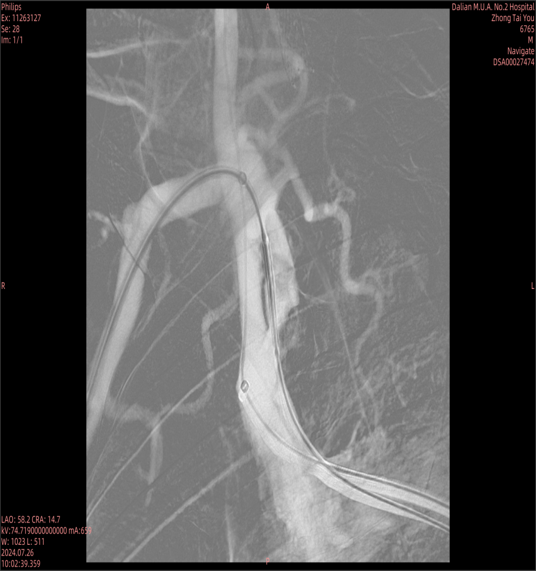

常规病变的精准支架释放:

即使是常规狭窄病变,采用CTA预定的角度(如 RAO 50° CRA 0°)也能实现支架的精准释放,确保完全覆盖病变且不影响重要分支。

图:支架精准释放

图:术中验证